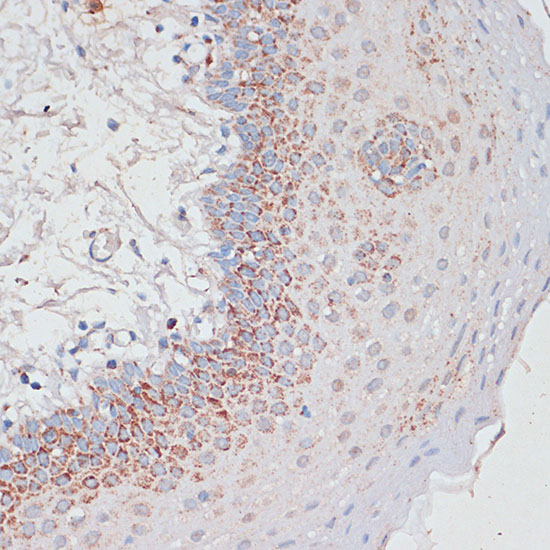

Immunohistochemistry of paraffin-embedded human liver damage using Desmoplakin at dilution of 1:100 (40x lens).

Immunohistochemistry of paraffin-embedded Human tonsil using Desmoplakin at dilution of 1:100 (40x lens).

Immunohistochemistry of paraffin-embedded Human colon carcinoma using Desmoplakin at dilution of 1:100 (40x lens).

Immunohistochemistry of paraffin-embedded Human breast cancer using Desmoplakin at dilution of 1:100 (40x lens).